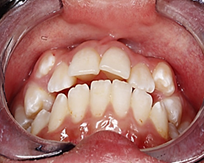

Al analizar las fotografías intraorales revelaron lo siguiente (Figura 2): Fotografía frontal: líneas medias dentales no coincidentes la inferior se encuentra con una desviación de 2 mm hacia la derecha, mordida abierta y caninos superiores ectópicos. (A). Fotografía lateral derecha (B) e izquierda (C): Clase II molar, clase canina no aplica debido a que los caninos no se encuentran en el arco.

Fotografía oclusal superior: Forma de arcada ovoide, apiñamiento en el sector anterior, palatinización de las piezas 1.2 y 2.2, piezas 1.3 y 2.3 ectópicas, paladar profundo (D). Fotografía oclusal inferior: Forma de arcada oval, lingualización de las piezas 4.5 y 4.6, ausencia de la pieza 3.7 (E). Fotografía de resalte: La sobremordida horizontal y vertical de -2 mm (F).